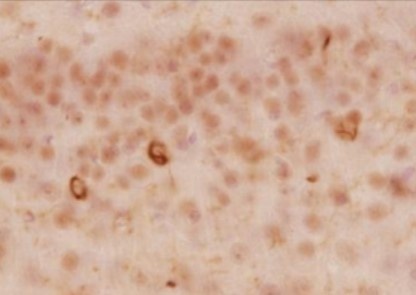

免疫組織染色

+

ビオチン標識二次抗体

ABC法

| 動物種 | マウス (6ヶ月齢、野生型、凝集α-シヌクレインを脳内に注入) |

| 部位 | 線条体 |

| サンプル | 50 µm厚 ビブラトーム切片 |

| 抗体濃度 | 1:1,000 |

| 染色法 | DAB染色 |

<データ提供>

東京大学大学院 医学系研究科 桑原先生、岩坪先生

[結果]

ビオチン標識抗体とABC法を組み合わせることで、二次抗体を用いた場合よりもバックグラウンドが抑えられ、明瞭に染色できた。